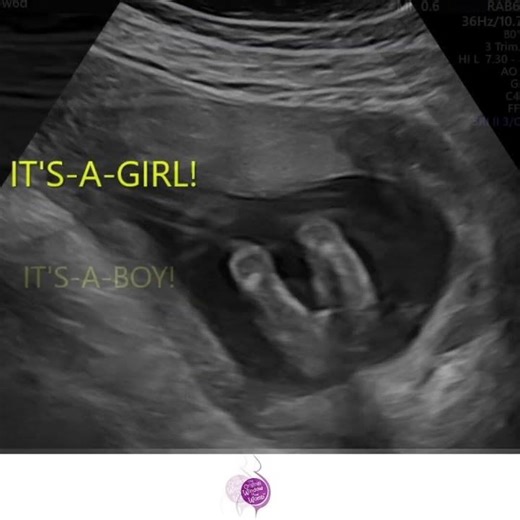

The Original Window to the Womb